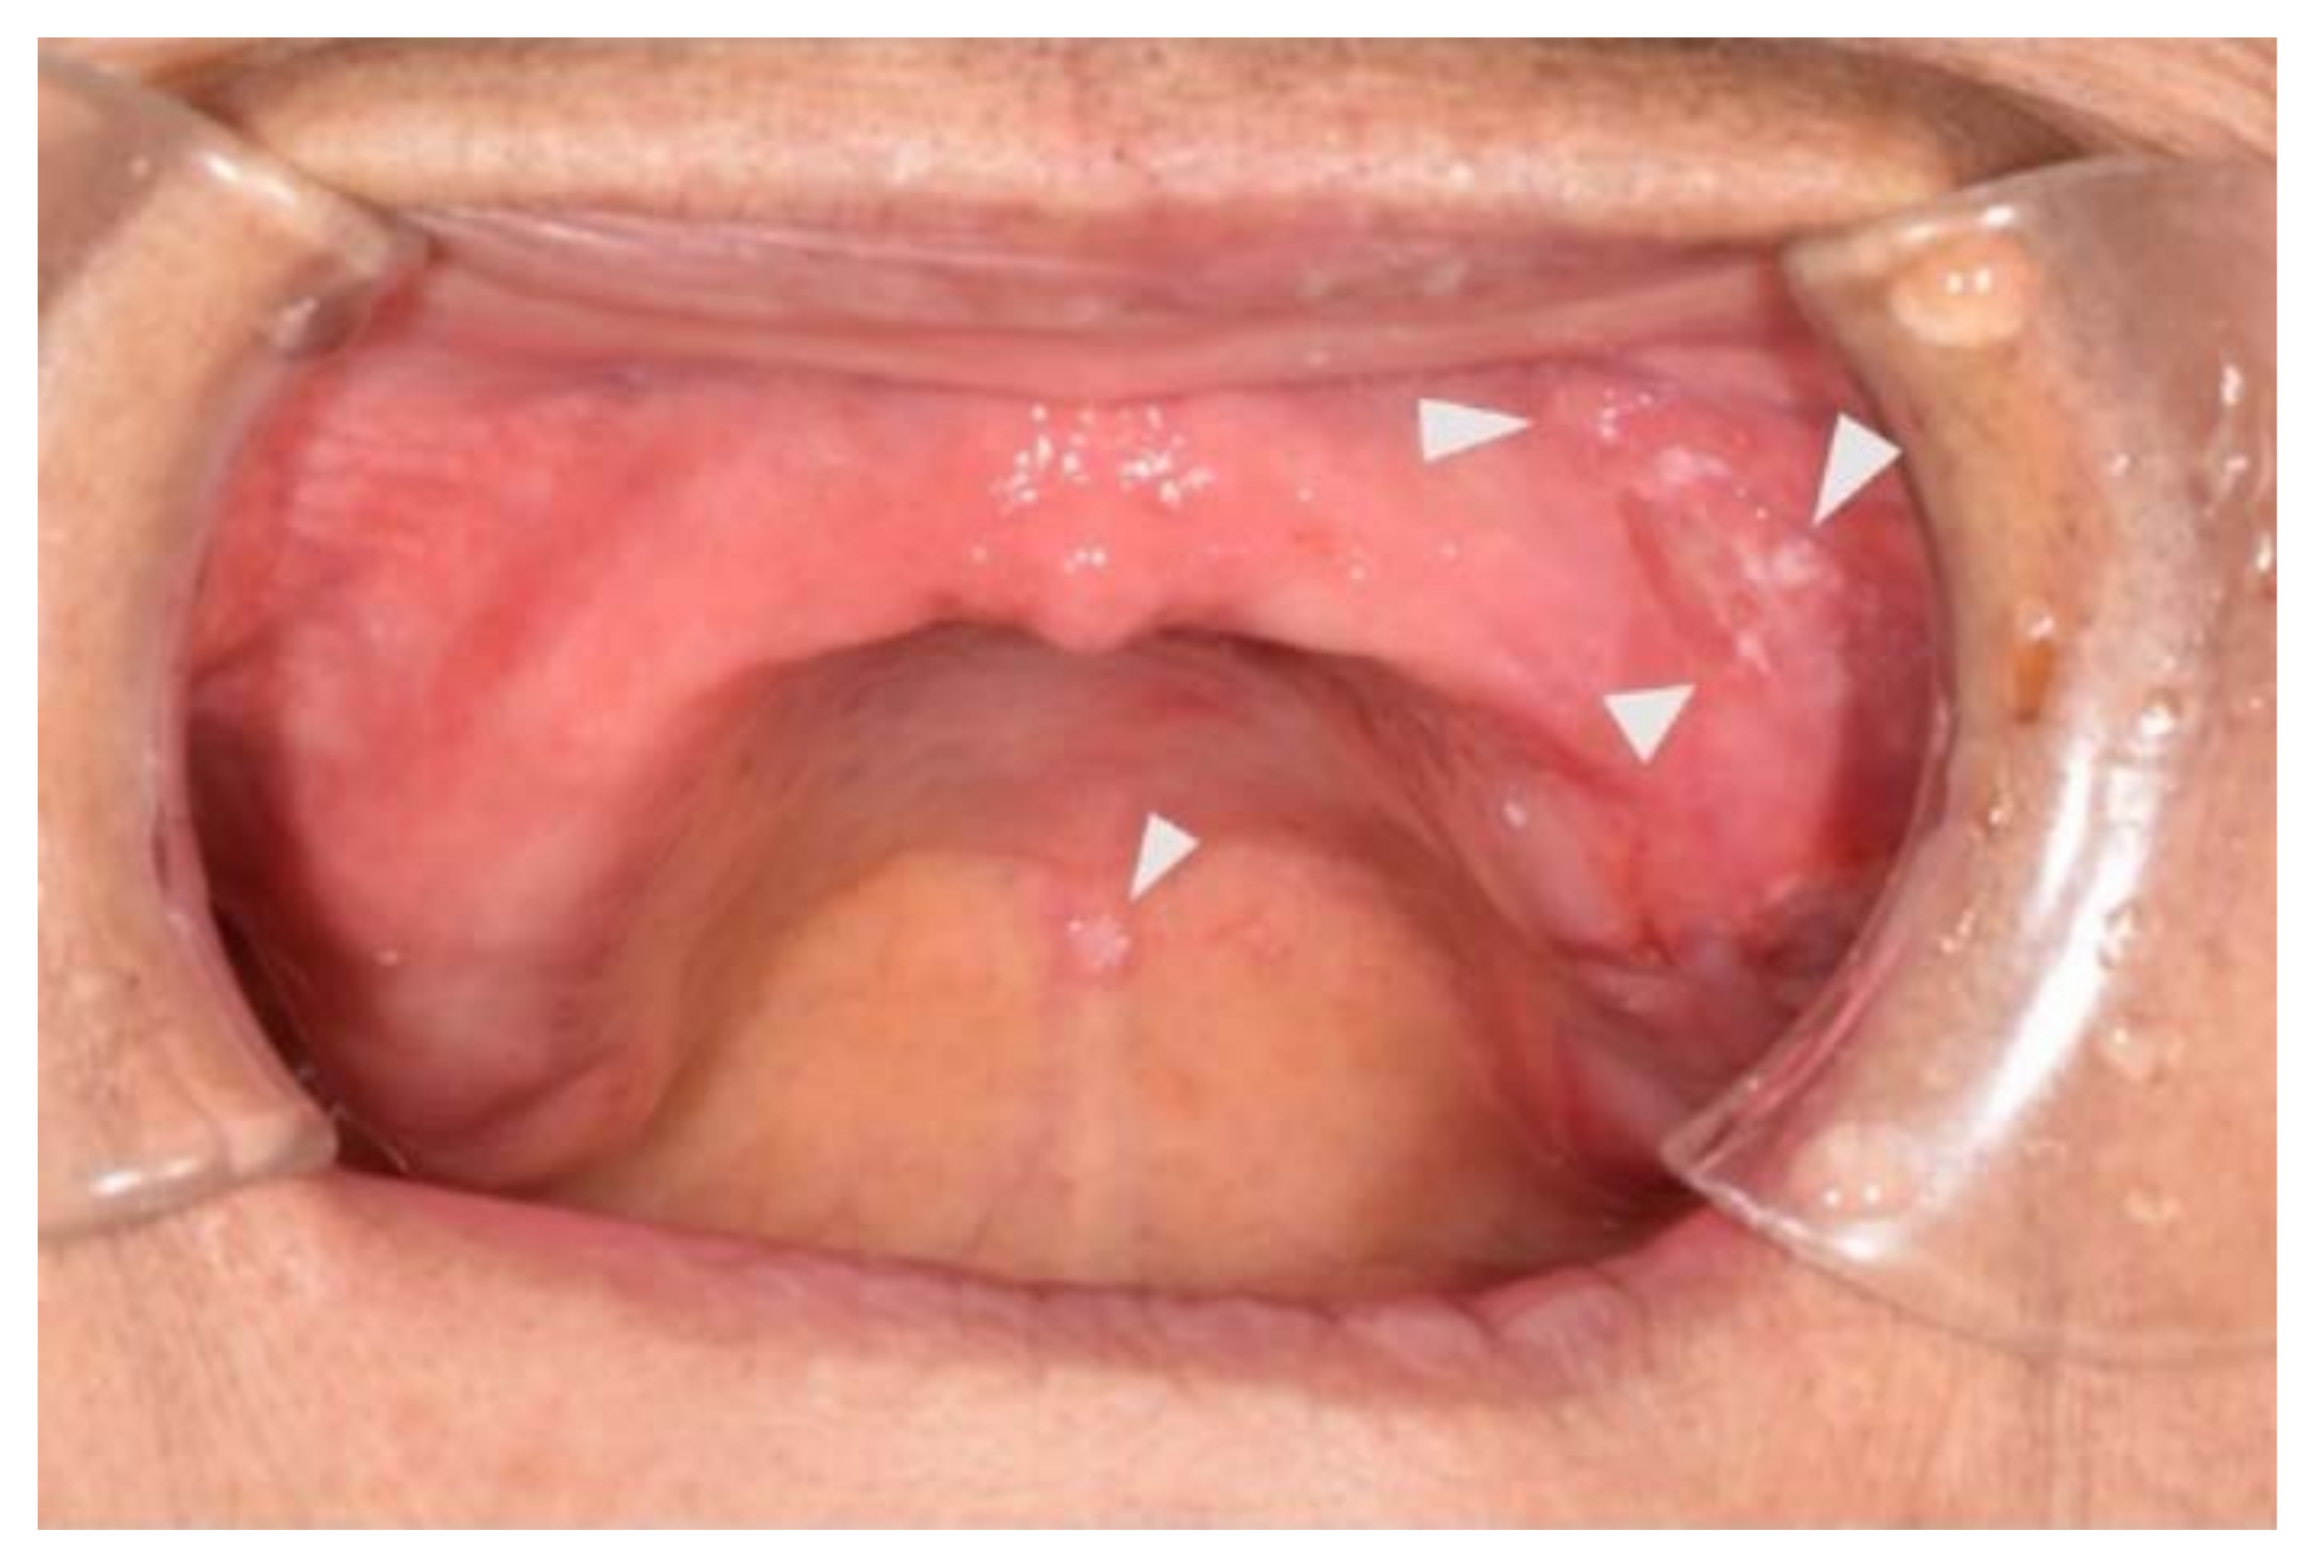

2.2. Initial Oral Evaluation